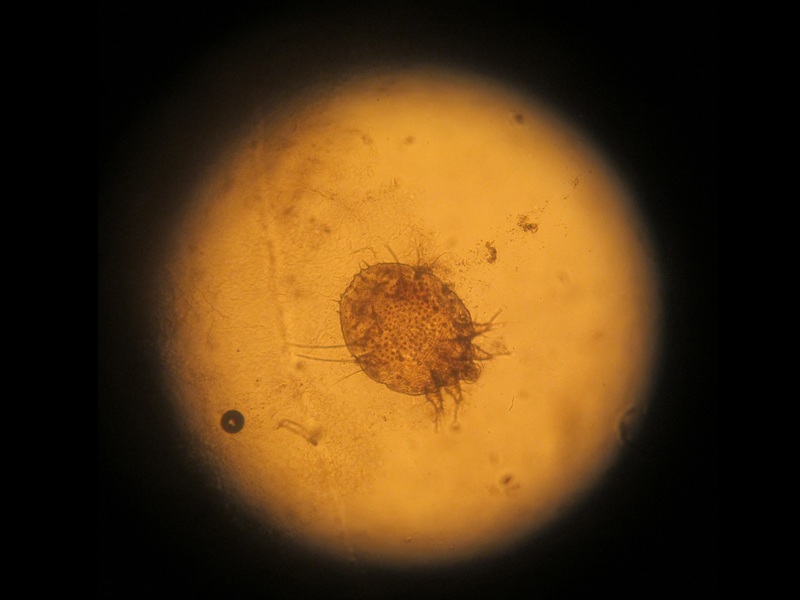

Scabies is a contagious skin infection caused by a mite. A mite is a parasite that buries itself under the host’s skin and breeds. This is the prime cause of the uncontrollable itching sensation. It is primarily a water-related disease; in most cases, transfer happens through direct skin contact.

The movement of mites primarily causes the itching sensation and is also the reason why treatment takes a little longer than expected. Scabies mostly spread from mites stuck under your nails from having scratched the affected area earlier. It can spread indirectly through objects too, which include bedding, clothing etc. Scabies can also spread from sexual intercourse in spite of using a latex condom.